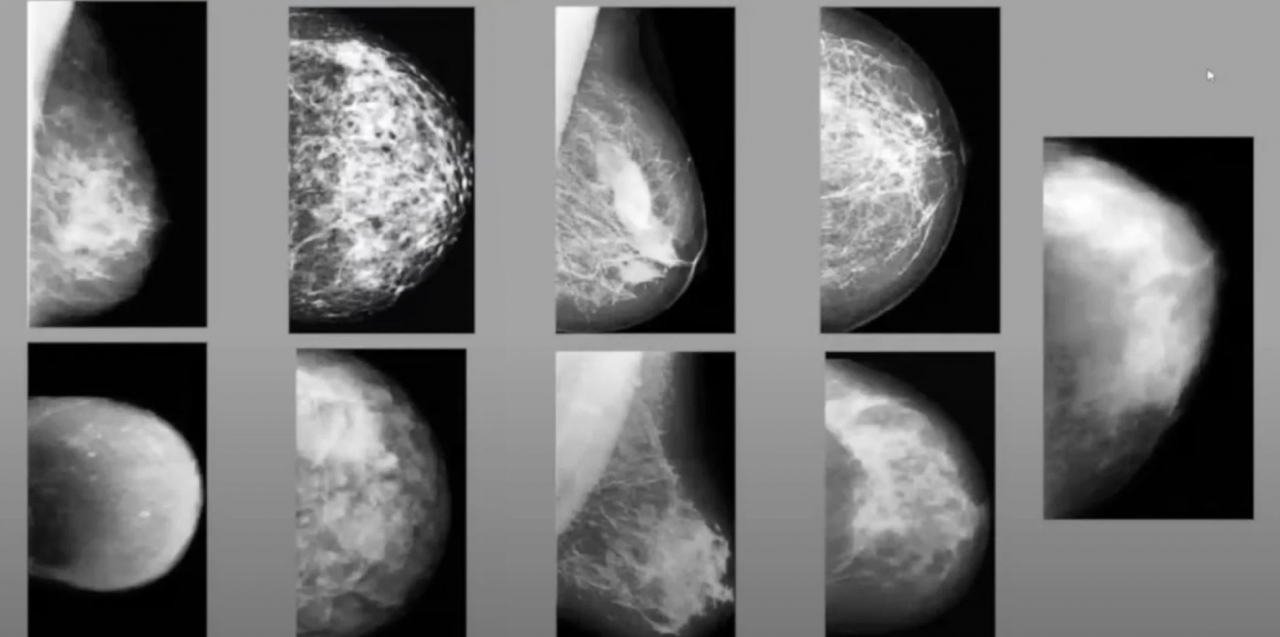

Калужская компания "Цельс", разработавшая систему искусственного интеллекта (ИИ) для анализа медицинских снимков, и группа ученых провели исследование, в котором оценили возможность применения систем поддержки принятия врачебных решений на базе технологий ИИ для контроля качества диагностики рака молочной железы. В ходе этого исследования система нашла пропущенные случаи болезни, рассказал в пятницу ТАСС коммерческий директор компании Артем Капнинский.

За время исследования искусственный интеллект проанализировал 2,9 тыс. маммографических исследований, которые ранее получили врачебную отметку "без патологий". Система отметила 389 исследований, на которые необходимо обратить внимание, 25 из них после пересмотра перевели в категорию повышенного риска, в двух исследованиях клинически подтвердилось наличие злокачественного новообразования.

Рак молочной железы занимает первое место в мире среди женских онкологических заболеваний по распространенности, что обусловливает значимость скрининговых программ по его ранней диагностике. Системы искусственного интеллекта для анализа цифровых медицинских изображений применяются, чтобы повысить эффективность диагностики онкологических заболеваний и снизить влияние человеческого фактора на анализ.